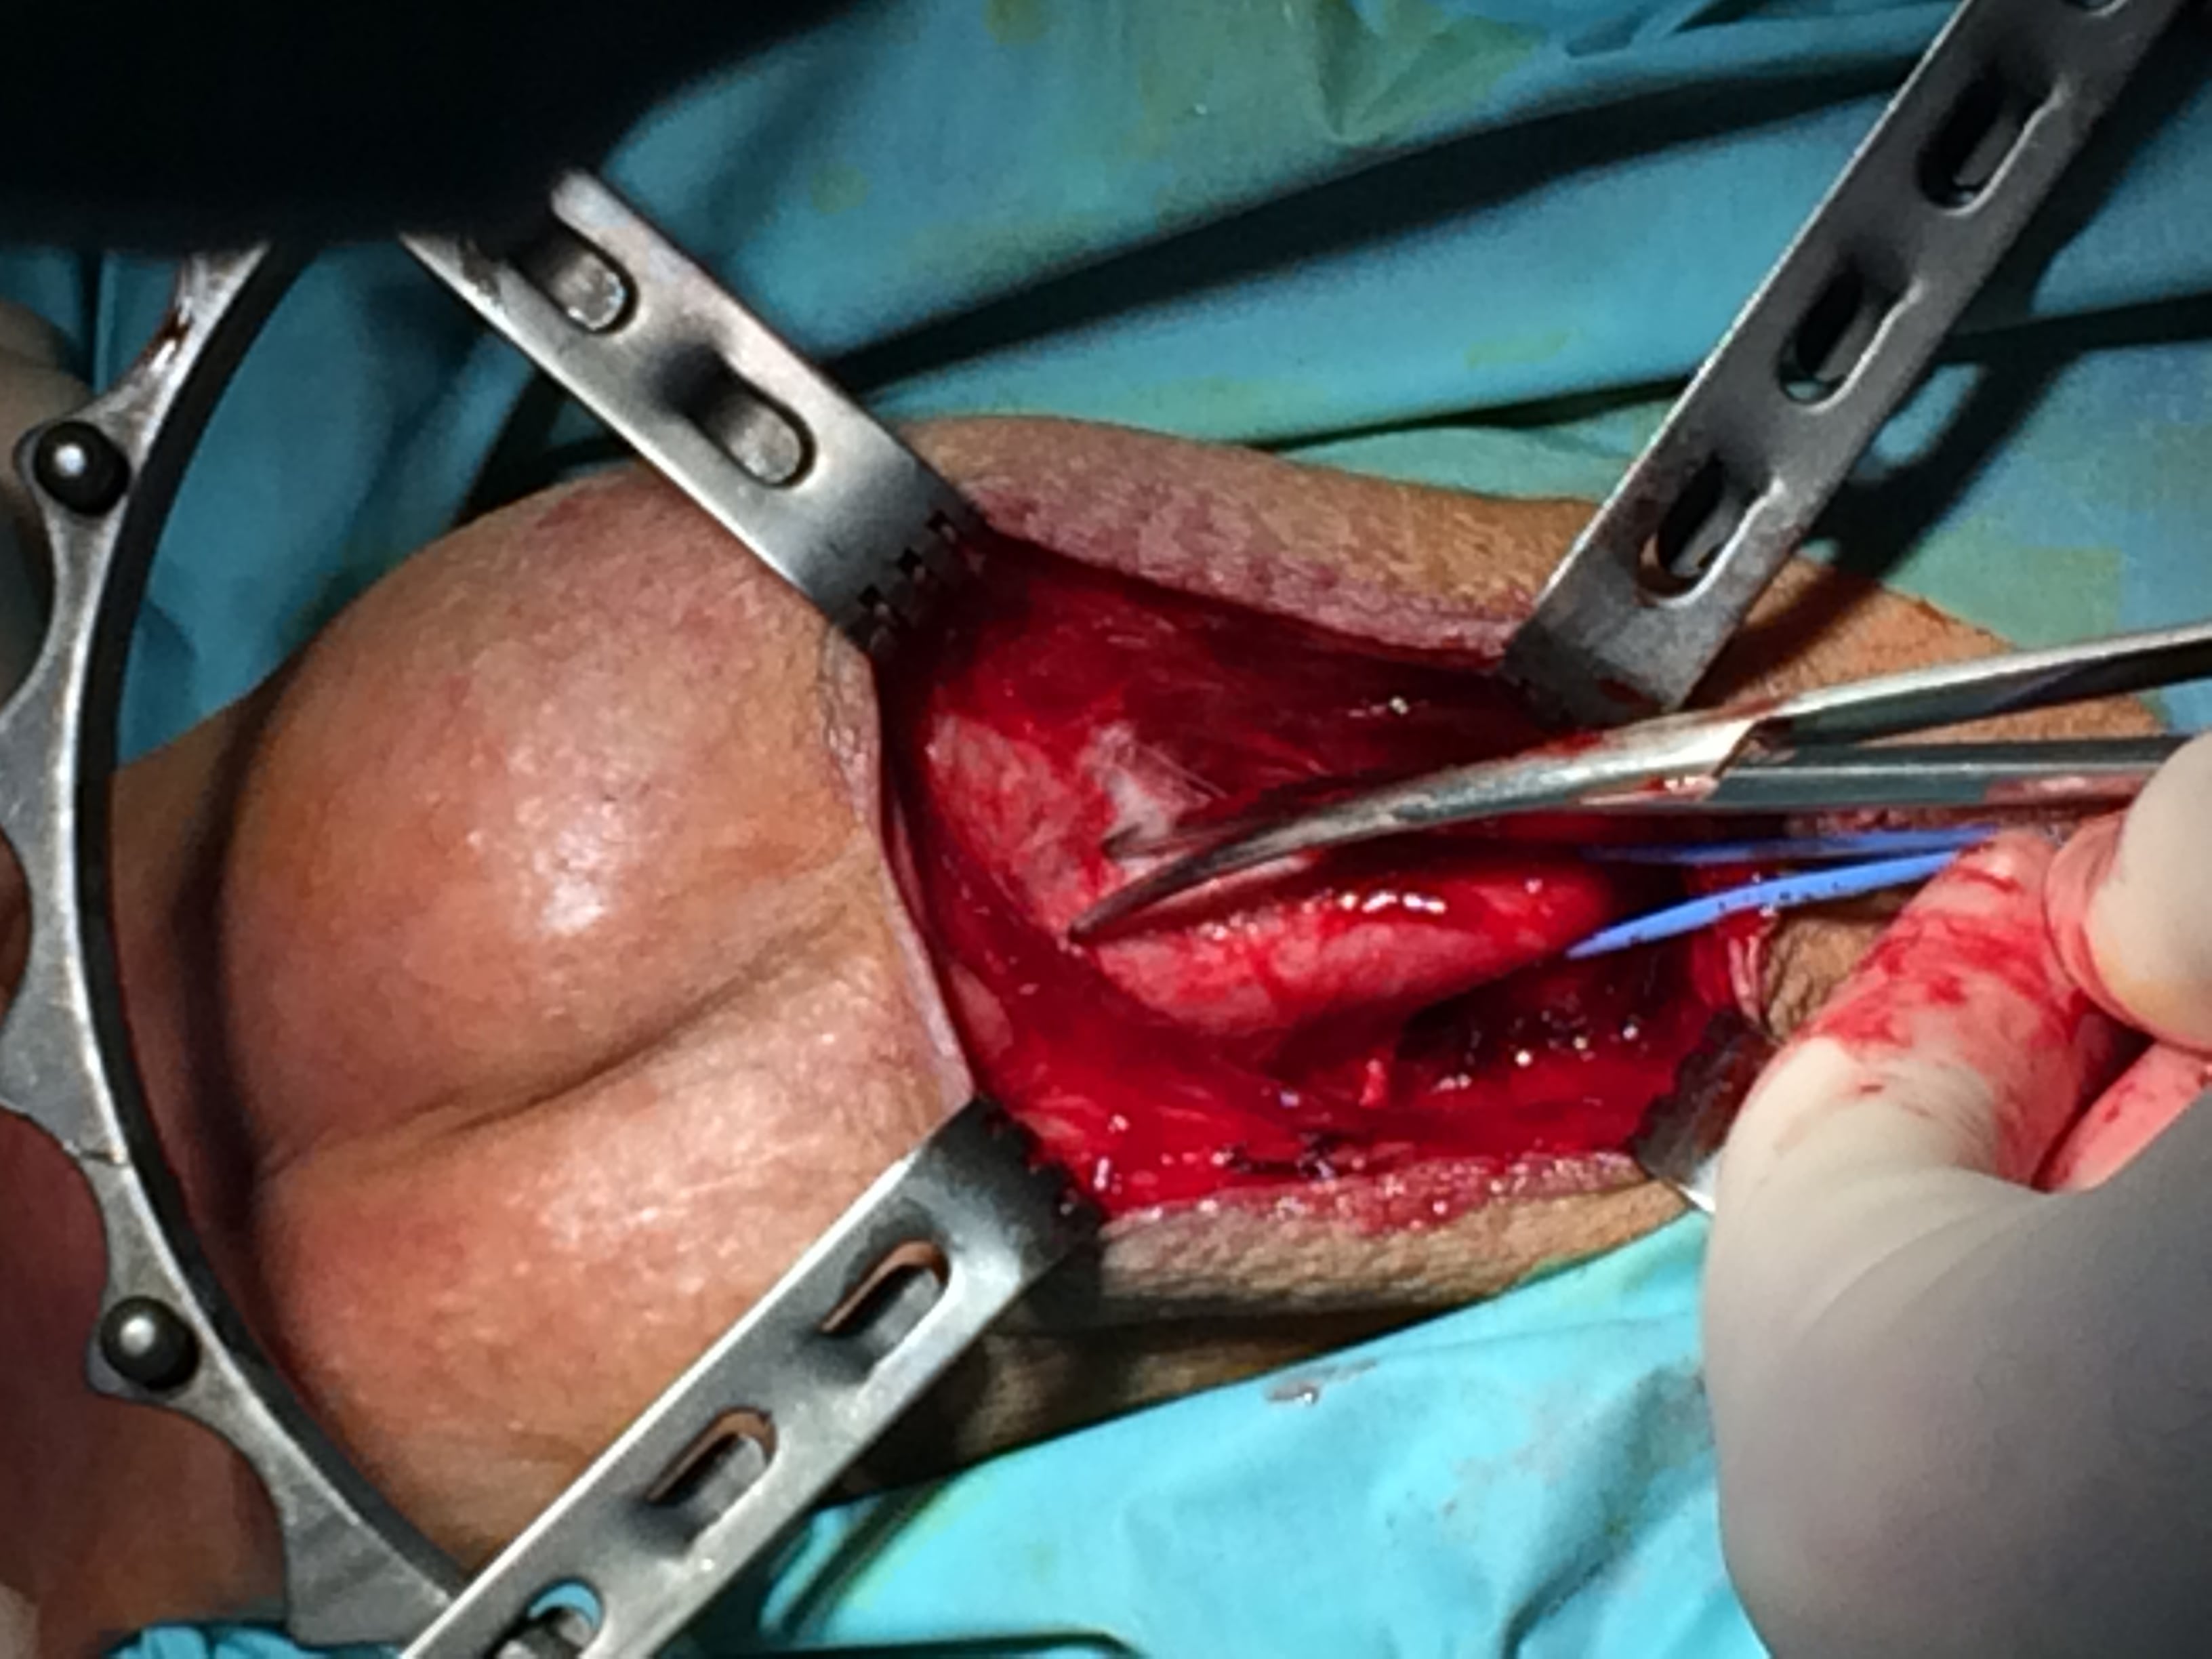

Ziar Medical – Intervenţia care a prilejuit discuţia noastră a fost o uretroplastie de substituţie. În ce a constat intervenţia? Spuneţi-ne două cuvinte despre pacient. Cum s-a desfăşurat?

Dr. Marcel Rad – Un pacient tânăr, etiologie neprecizată a stricturii, ceea ce numim noi iatrogenă, fără a putea identifica anume o cauză, o strictură care a mai fost tratată anterior prin două intervenţii endoscopice, cea din urmă ducând la extinderea foarte mult a zonei de strictură. Pacientul a fost informat corespunzător despre opţiunile de tratament, iar el, trecând prin astfel de intervenţii minim invazive, în prima fază chiar s-a gândit să o aibe şi pe a treia.

Când i s-au prezentat posibilele complicaţii şi rata de succes, lucrurile au stat puţin altfel. Pacientul a fost externat ieri (după patru zile n.r.), este foarte bine. A beneficiat de uretroplastie cu mucoasă bucală. S-a prelevat un lambou de mucoasă de 6 cm. lungime pe 2 cm. lăţime, cu suturarea zonei donatoare. La nici 12 ore postoperator pacientul a început să mănânce.